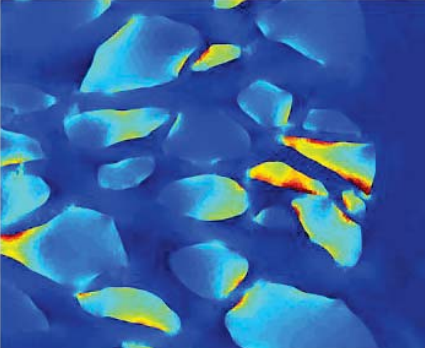

image

• Test-retest reproducibility of atomic force microscopy measurements of human trabecular meshwork stiffness

• L Kagemann, J Candiello, G Wollstein, H Ishikawa, RA Bilonick, IA Sigal, C Jonescu-Cuypers, PN Kumta, JS Schuman

• Modeling and Artificial Intelligence in Ophthalmology, 2(4), 34-43, June 2020.